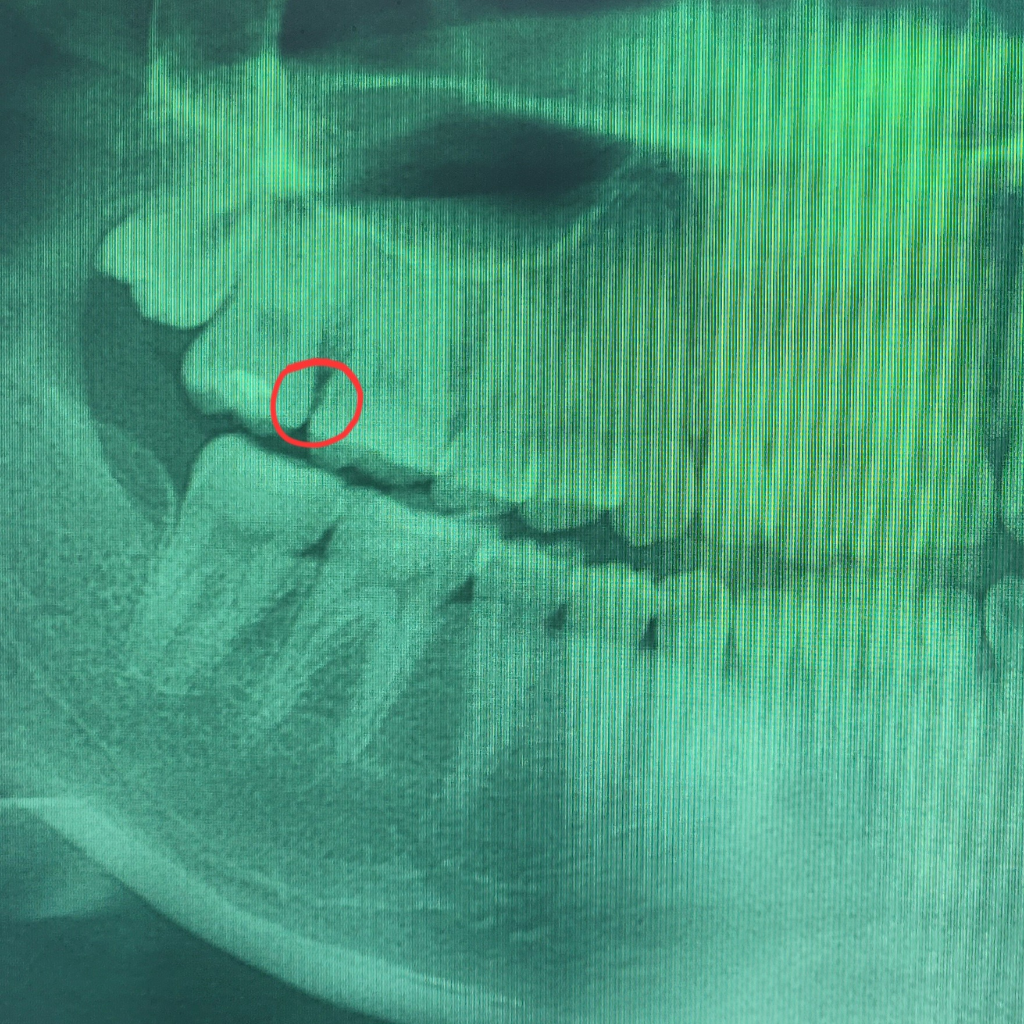

사진이 흐릿하여 명확한. 답변을 드리기는 힘들고 치근단 사진을 찍어보시고나서 올려주시면 도움을 드릴 수 있습니다.

파노라마 상에서 저렇게 보인다면 작은 엑스레이 사진을 찍어봐야 정확히 알수 있을것같습니다. 충치일 가능성이 높으니 가셔서 다시 검진을 받아보세요.

인접면 충치의 가능성도 있어보입니다. 인접면 우식에 대해 좀 더 자세히 보려면 치근단 방사선사진 중 교익방사선사진을 촬영해봐야 합니다

만약 충치가 맞다 하더라도 아주 크게 진행된 상태는 아니라고 보여집니다

평소 해당 부위 음식물이 자주 끼거나 그랬다면 충치일 확률이 좀 더 높습니다